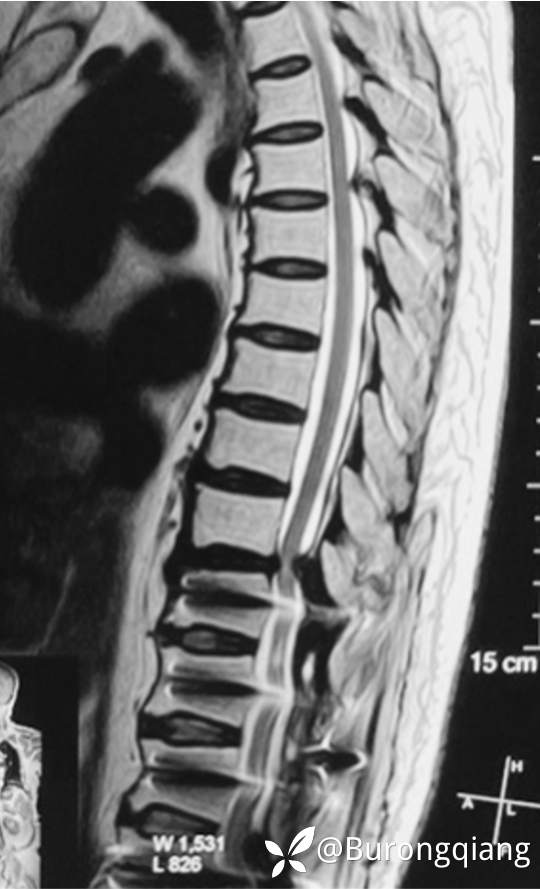

简要病史:患者述2年前无明显诱因出现双下肢大腿憋胀不适症状。外院进一步检查后诊断胸腰椎椎管狭窄,于外院行胸腰椎多节段椎管减压内固定手术治疗,术后症状改善明显,术后10个月再次逐渐出现双下肢麻木无力症状,左侧症状明显,行走时偶有打软腿不适,1年前摔倒致左踝关节骨折,给予内固定手术治疗,术后一直未能下地活动,双下肢麻木无力明显,二便正常。采取保守对症治疗,症状近来逐渐加重。

查体:胸背部无明显异常,原手术切口愈合良好;胸背部无明显压痛,双下肢皮肤感觉大致正常,双下肢肌力明显减弱,双侧股四头肌、臀中肌及踝关节背伸跖屈活动肌力2-3级,双侧膝腱反射、跟腱反射活跃,双侧直腿抬高试验阴性,双侧髌阵挛阴性,双侧踝阵挛阳性,双侧巴彬斯基征阳性。

临床诊断:胸椎管狭窄